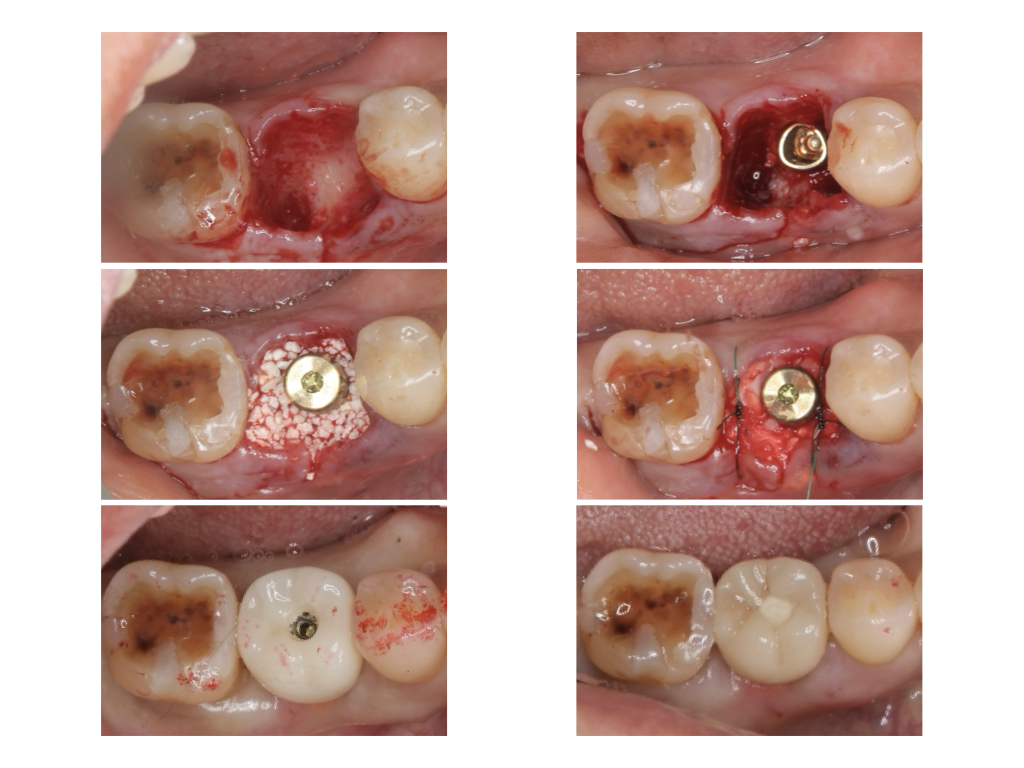

隣在歯の歯槽骨まで再生!

当院では、奥歯(大臼歯部)において、抜歯と同時にインプラント手術を行う「抜歯即時埋入」に対応しております。

治療の特徴とメリット 従来の方法では、抜歯後の治癒を待ってからインプラント手術を行うため、どうしても治療期間が長くなり、手術も2回に分ける必要がありました。「抜歯即時埋入」ではこれらを一度に行うため、以下のメリットがあります。

• 手術回数が1回のみ: 患者様の精神的・肉体的な負担を軽減します。

• 治療期間の短縮: 最終的な被せ物が入るまでの期間を大幅に短くできます。

技術と適応について この治療法は高度な技術と経験を要するため、すべての歯科医院で行われているわけではありません。また、患者様の骨の状態や感染の有無によっては適応が難しいケースもございます。 当院ではCT撮影などの精密検査を行い、安全で確実な治療が可能かどうかを慎重に診断しております。

Step 1: 外科処置(抜歯・埋入・組織再生) 対象となる歯を抜歯すると同時に、インプラント体(フィクスチャー)の埋入を行います。その際、インプラント周囲の骨が不足している部分には「骨補填剤」を填入し、丁寧に縫合します。外科的侵襲を1回に集約することで、患部の回復を早めます。